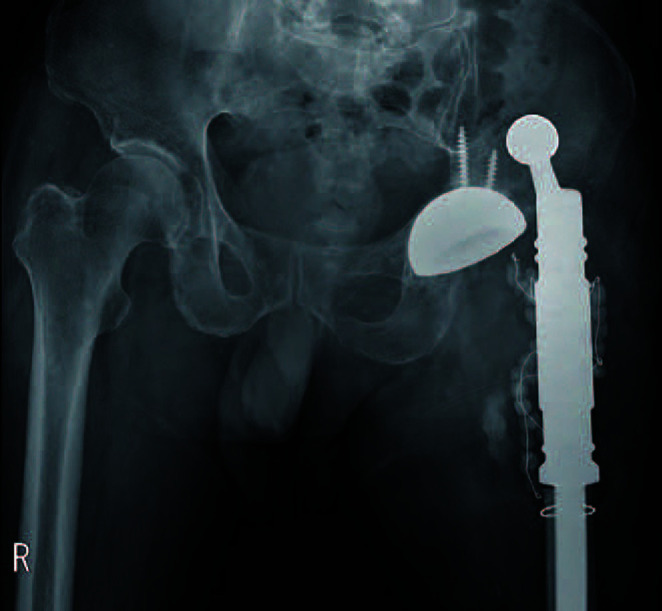

全髋关节置换术后脱位发生率约为 1%,但翻修手术后的发生率要高得多。为防止脱位,建议使用较大的股骨头,并引入了双活动股骨头。然而,在关节周围软组织挛缩的病例中,将双活动股骨头缩小至髋臼组件是很困难的。一位72岁的男性患者因假体周围关节感染而接受了两阶段的MUTARS®翻修手术。翻修手术两个月后,髋关节脱位,尝试了人工复位,但脱位再次发生。在另一次使用双活动轴承进行翻修时,髋关节周围的软组织太紧,无法缩小。为了解决这个问题,首先将双活动度轴承头重新定位到髋臼窝中,然后组装植入物的骺端部分。

Dislocation after a total hip arthroplasty occurs in approximately 1% of patients; however, the frequency is much higher after revision surgery. To prevent dislocation, use of a larger femoral head is recommended, and a dual mobility femoral head has been introduced. However, reducing the dual mobility femoral head to the acetabular component is difficult in cases involving contracture in the soft tissue around the joint. A 72-year-old male patient who developed a periprosthetic joint infection underwent two-stage revision surgery using MUTARS®. Two months after the revision, the hip joint became dislocated and manual reduction was attempted; however, dislocation occurred again. During another revision using a dual mobility bearing, the soft tissue around the hip joint was too tight to reduce. The problem was overcome by first repositioning the dual mobility head into the acetabular socket, followed by assembly of the diaphyseal portion of the implant.